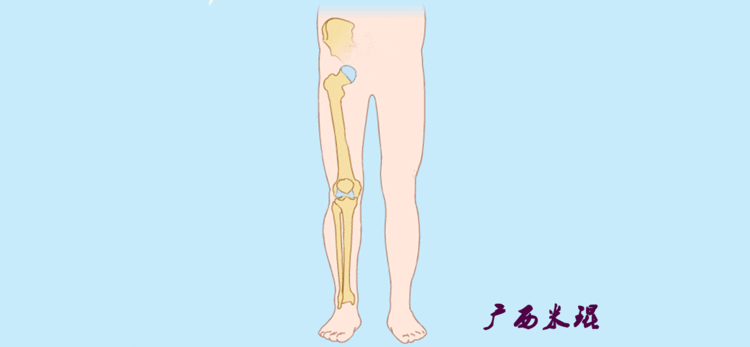

(2)机械轴机械轴是连接近端和远端关节中心点的直线。

机械轴要分前后位及侧位,站立前后位(也就是冠状面)股骨头中心与踝关节中心的连线通过膝关节中心,这是下肢的机械轴线,也就是下肢力线,常说Mikulicz线。冠状面的力线评估在临床工作中最常用、最基础、最重要。

站立侧位(矢状面)股骨头中心与踝关节中心的连线也通过膝关节中心,这也是下肢的机械轴线,这也是下肢力线。

(3)垂直轴也就是下肢的负重轴,它是身体的纵轴线,与地面垂直,由于双髋比双踝的距离宽,所以垂直轴与下肢力线(机械轴)存在3°的外翻。